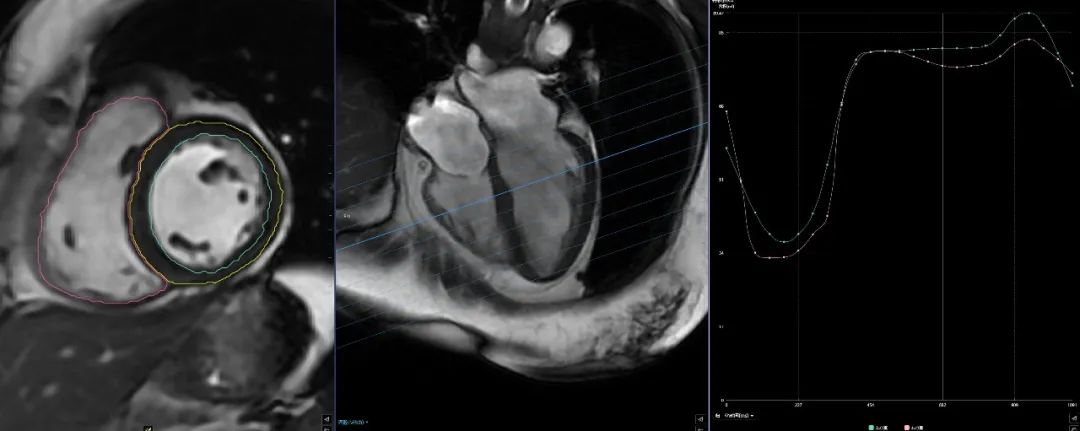

(二)心臟磁共振“一站式”檢查,通過多種掃描序列對心臟進行綜合成像,具有無電離輻射、大視野、任意平面成像等優(yōu)點,可重復(fù)性強,空間、時間和軟組織分辨力良好,還可以實現(xiàn)在體組織“病理影像化”。

圖片

心臟磁共振“一站式”檢查